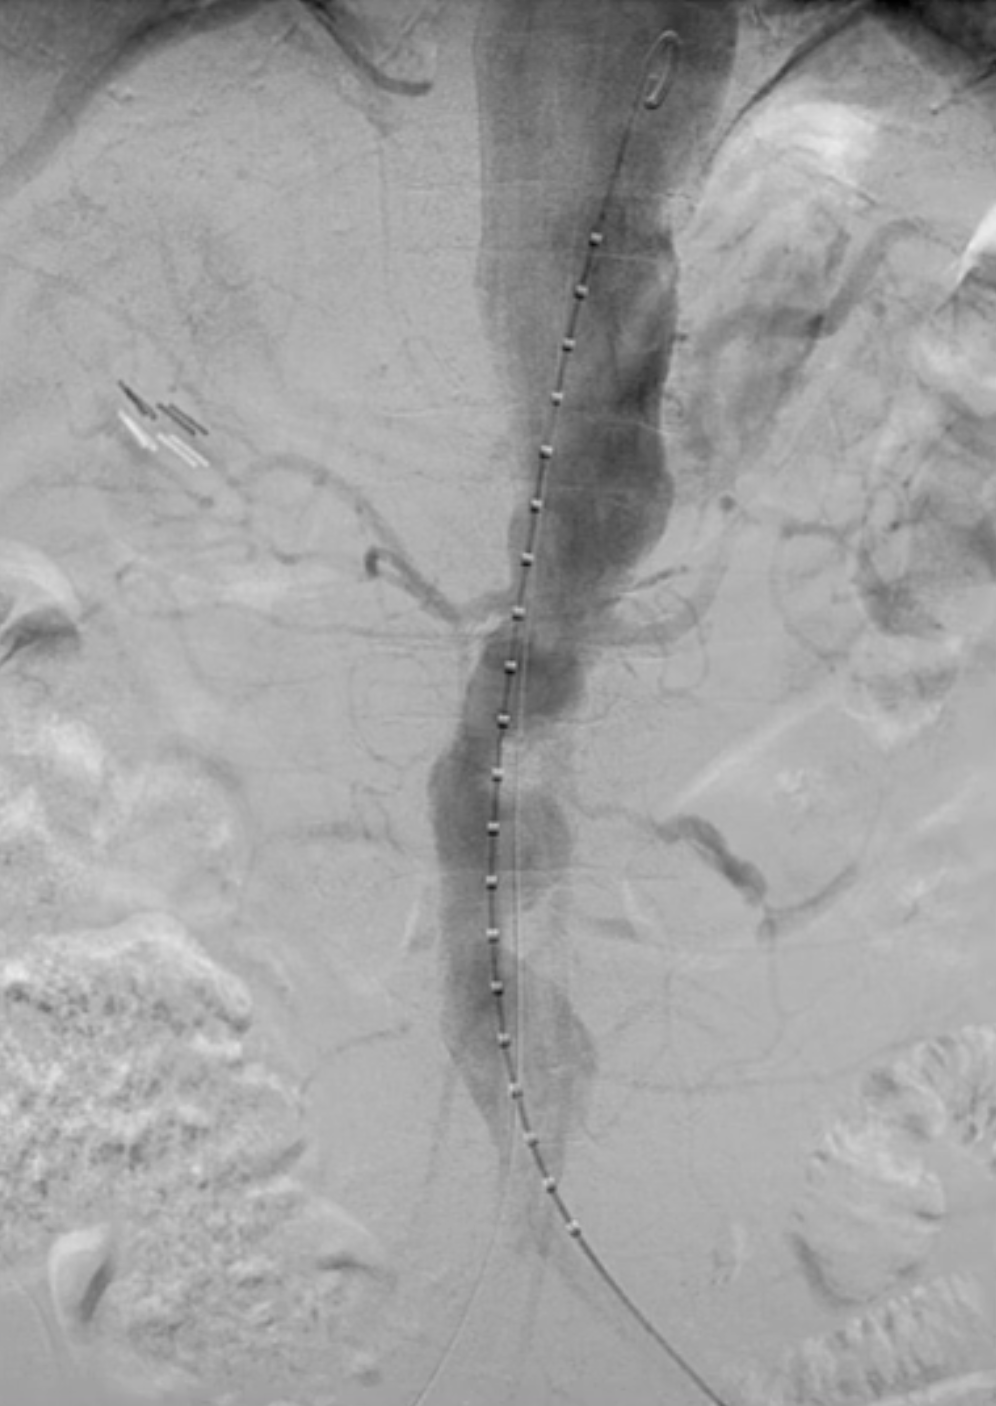

术前造影

使用12Fr DrySeal Flex亲水涂层导引鞘和7F可调弯鞘配合导丝超选入内脏动脉。

在左肾动脉预植入Visi pro裸支架。

对其他目标内脏血管重复上述操作,在较弯曲的血管中选择较短的支架更为方便。在肠系膜上动脉进行必要的侧位造影。